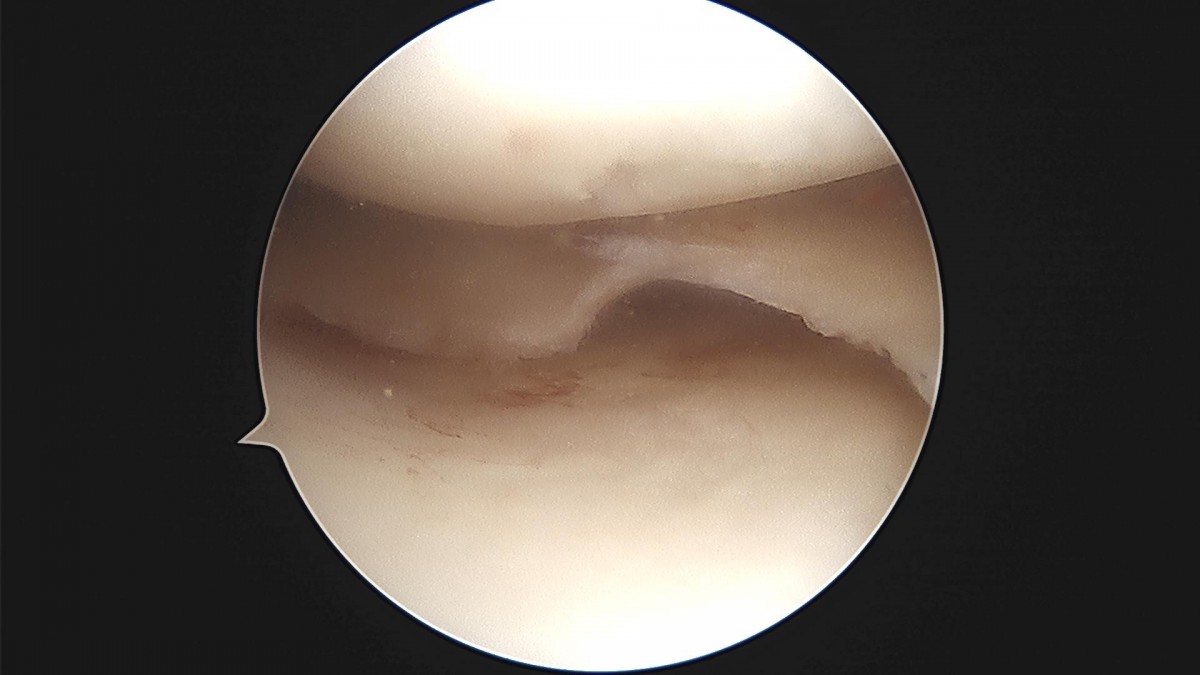

이재상원장님 무릎 반월상 연골판 절제술 정수O 환자

작성자 최고관리자 댓글 0건 조회 2,161회 작성일 23-04-18 12:06